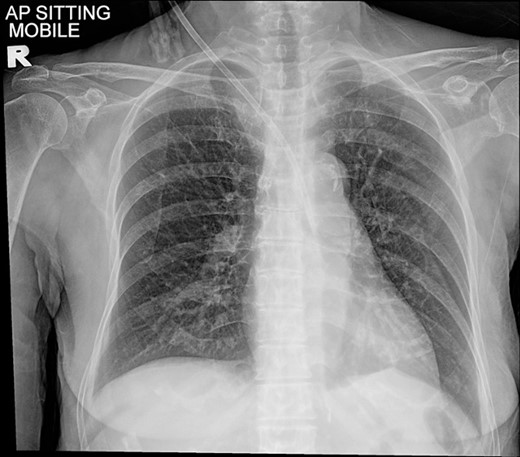

A 77-year-old lady with underlying type 2 diabetes mellitus, hypertension, and newly diagnosed end-stage renal failure presented with a 1-week history of vomiting, diarrhoea, and loss of appetite. Clinically she was uraemic necessitating haemodialysis. A vascular access was attempted using a 15 cm, 12 Fr haemodialysis catheter through her right internal jugular vein under ultrasound guidance. However, a chest radiograph post procedure showed a malpositioned catheter (Fig. 1). A computed tomography angiogram of the neck and thorax with 3-dimensional image reconstruction revealed a through-and-through right internal jugular vein puncture resulting in an inadvertent right brachiocephalic artery cannulation. The puncture point was identified near the bifurcation of the right brachiocephalic artery with the tip lying just superior to the aortic valve (Fig. 2). She was urgently referred to the cardiothoracic centre for further management.

Chest radiograph showing a malpositioned central vein catheter.